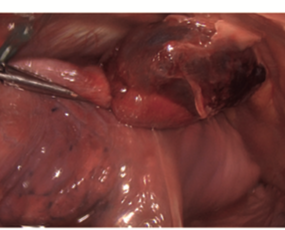

Resultados: La VTC reveló un infarto del segmento lingular inferior por torsión pulmonar, llevando a la realización de una resección segmentaria de la língula sin complicaciones.